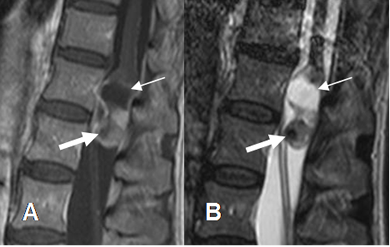

Fig 237 A. Astrocitoma.

A: RM sagital en T1 simple, B: RM sagital en T1 con contraste y C: RM sagital en T2. Lesión expansiva en el cono medular, hipointensa en T1, hiperintensa en T2 y que realza con el contraste, sin porción quística, por astrocitoma.

Fig 237 B. Astrocitoma.

A: RM axial en T2. Medula espinal engrosada y ocupando todo el canal medular.

B: RM sagital en T1 simple y C: RM sagital en T1 con contraste. Extenso engrosamiento medular, que realza con el contraste, secundario a astrocitoma.

Fig 238. Diseminación leptomeningea.

A: RM sagital en T2, B: RM sagital en STIR y C: RM sagital en T1 con contraste. Imágenes redondeadas y de defecto de llenado, sobre la medula distal y las raíces de la cola de caballo, que realzan con el contraste y corresponden a diseminación leptomeningea, por un linfoma.